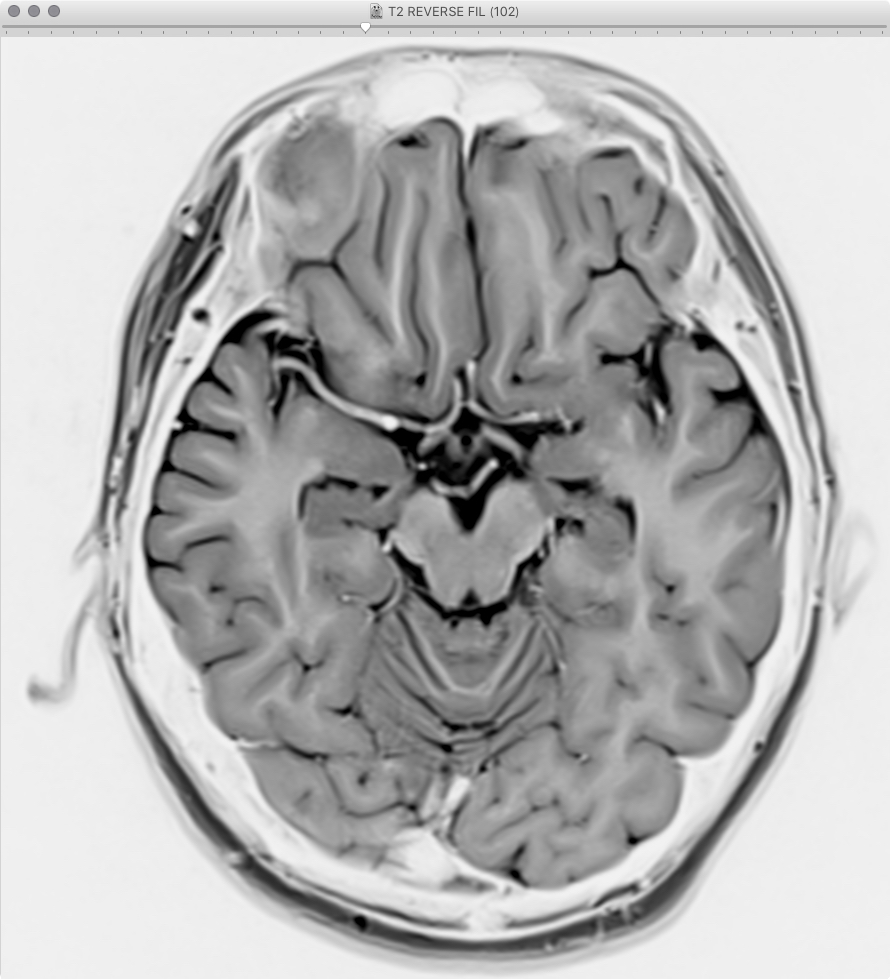

画像サンプル |

---|